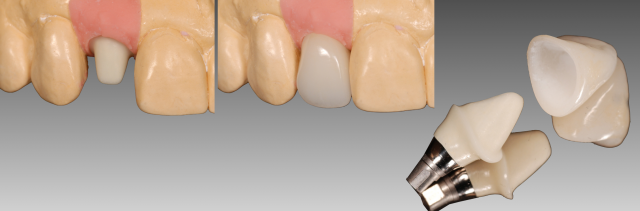

Three months after implant placement and confirmation of implant integration, an implant provisional was used to shape the soft tissue profile. (Fig. 4) Utilizing a custom impression coping, the exact soft tissue contours were transferred to the technician. (Fig. 5)

The definitive abutment chosen was a UCLA-metal ceramic abutment. The abutment was designed with ceramic added over the entirety of the surface (not just sub-gingival) so that an all-ceramic restoration (e.max) could be used for the crown. The benefit of the entire surface being baked with ceramic is that if desired, the abutment could be etched and silanated to allow the restoration to be bonded with resin cement. (Fig. 7)

Variations in the abutment design do exist. The decision to build the entire abutment with ceramic depends on the amount of space present. If required due to space limitations, the occlusal part of the abutment can either be opaqued only or left either as metal. (Fig. 8)